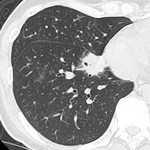

[バーチャル抄読会・HawksRad編](42) 肺炎クラミジア:薄層CTにてのマイコプラズマ、肺炎球菌の所見との比較 2010-08-26